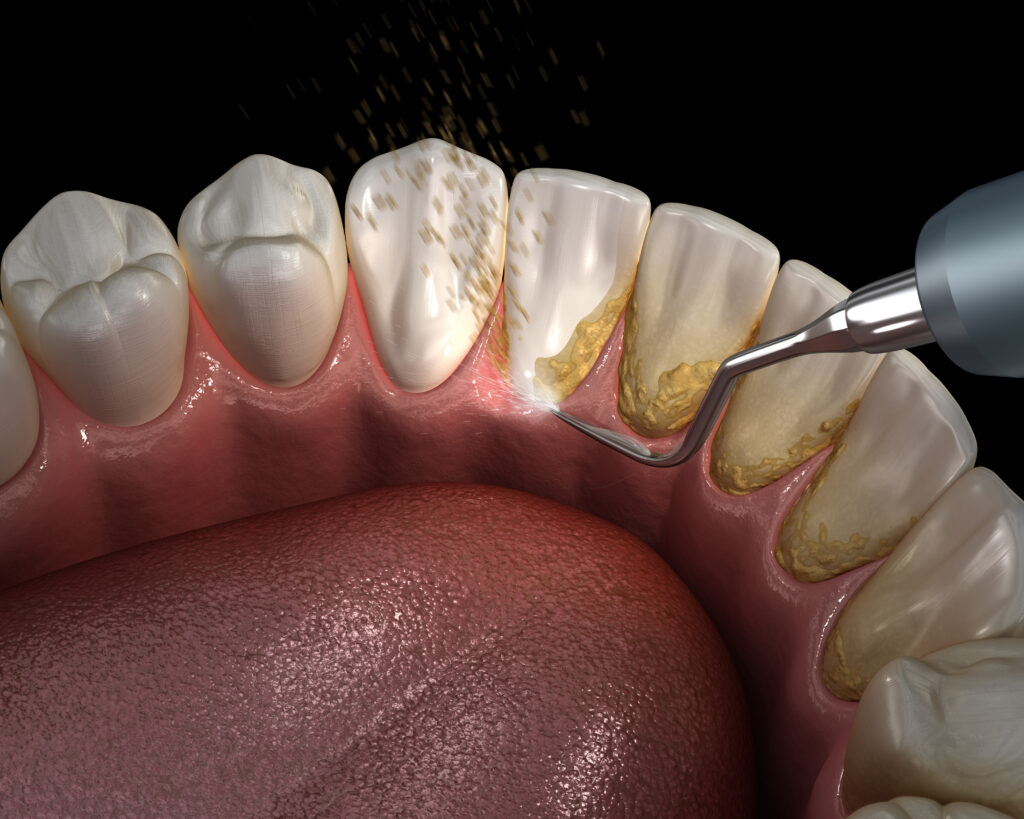

For patients with active gum disease, it’s crucial to treat the condition before undergoing the All-on-4 procedure. At Advanced Dental Artistry, we either provide periodontal treatment in-house or refer you to a trusted specialist to stabilise your gum health.

- Periodontal treatment: Essential to manage and stabilise gum health. This may involve deep cleaning (scaling and root planing), antibiotic therapy, or other procedures to reduce infection and inflammation.